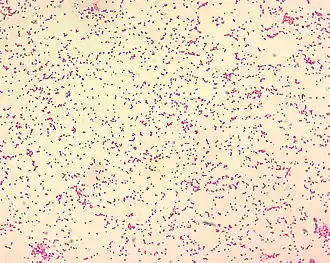

Brucellose (bij mensen Maltakoorts) is een infectieziekte bij mensen en zoogdieren die wordt veroorzaakt door bacteriën uit het geslacht Brucella. In 1887 werd deze bacterie voor het eerst geïsoleerd door de Britse militair chirurg Sir David Bruce op Malta.

Het was de Amerikaanse [[Alice Catherine Evans]] (29 januari 1881- 5 september 1975) die voor het eerst de link legde tussen Maltakoorts en ziekte van Bang. Dat het drinken van koemelk besmet met Brucella Abortus tot gezondheidsproblemen zou zorgen bij mensen vond zij een interessant fenomeen. Ze ging daarom op onderzoek uit en vroeg Dr. Eichorn, hoofd van de afdeling pathologie of hij meer gevallen kende waarbij ogenschijnlijk gezonde dieren die bacteriën uitscheidden die mensen konden besmetten. Hij wees haar vervolgens op de Maltakoorts. Evans ontdekte dat de bacterie inderdaad staafvormig is, maar dat ze soms zo kort zijn dat ze er rond uit zien[9]. Deze bacterievorm, die noch kokken noch een bacil was, werd daarom coccobacillen genoemd. Toen Evans haar werk in 1918 publiceerde werd het met veel kritiek ontvangen, de link werd gezien als medische godslastering. Daarnaast was ze ook nog eens een vrouw en had ze geen PhD[10]. In 1920 zou haar werk bevestigd worden door Karl F. Meyer en collega's. Vanaf dat moment ging men de term brucellose hanteren ter ere van zijn eerste ontdekker David Bruce. In de vier jaar die daar op volgden kwamen dezelfde bevestigingen van tien andere onderzoekers uit zeven verschillende landen[9].